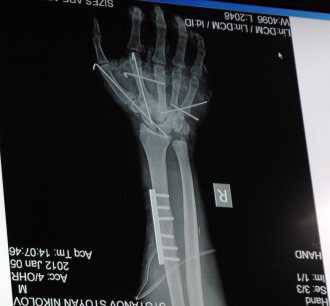

Зимната обстановка през последните седмици – студ и поледица, доведоха до повече травми. Най-честите наранявания през този сезон са именно счупвания в областта на малките стави – китка, рамо, глезен, както и на тазобедрената става. Затова Медицински комплекс „Доверие“ ще проведе безплатни прегледи за ортопедични и травматологични заболявания. Те ще се състоят тази събота (30.01. 2016) от 08:30 до 12:30 часа. …